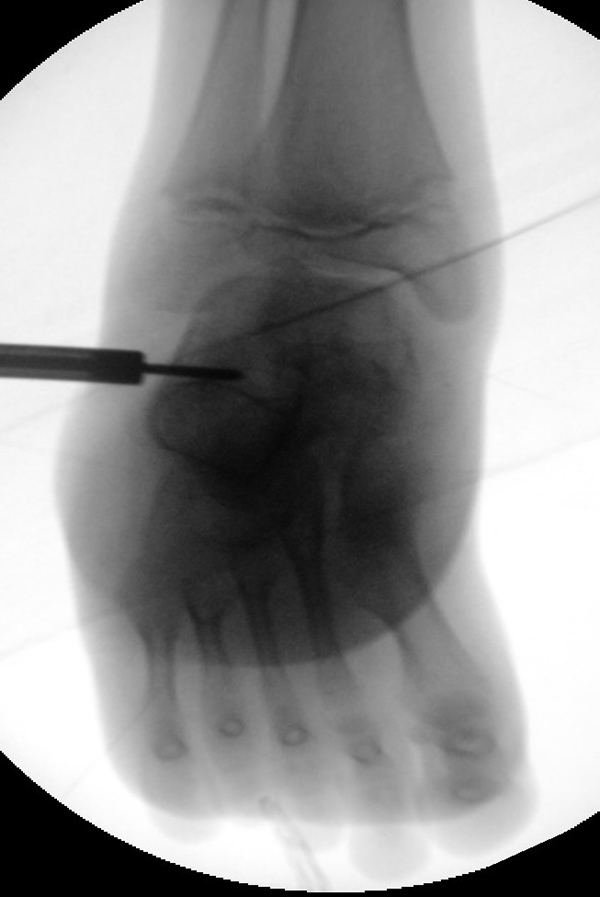

=> Risikoabwägung der radiologisch leicht erhöhten Strahlenbelastung intraoperativ

In der minimalinvasiven Fußchirurgie ist es unabdingbar, die Fräse in ihrer Position zum Knochen radiologisch zu kontrollieren, damit vulnerable Wachstumsfugen oder angrenzende Gelenke nicht verletzt werden. Zu diesem Zweck werden mit einem Bildwandler während der Operation die genaue Position der Fräse und der Osteotomieverlauf überprüft, was die Strahlenbelastung im Vergleich zu offenen Verfahren erhöht. Diese Strahlenbelastung hat potenziell einen schädigenden Einfluss auf den noch blutbildenden Knochen von Heranwachsenden. Gesicherte Landmarken am Fuß können die notwendige Zahl der Röntgenbilder und damit die Strahlung minimieren. Ist es erforderlich, mehrere Knochen zu osteotomieren, wie zum Beispiel im Bereich der Kleinzehen, werden anhand der Landmarken kleine Injektionsnadeln auf Höhe der geplanten Osteotomien vorgelegt und radiologisch im Bildwandler (BV) dokumentiert (Abb. 11). Ein solches Bild schafft eine gute Orientierung, sodass auf radiologische Kontrollen intraoperativ weitestgehend verzichtet werden kann.

Abb. 11: Lokalisation mehrerer Stichinzisionen mit einem Röntgenbild.

Zum Lesen der Bildbeschreibung und zur Vollansicht bitte das Bild anklicken. Bild: A. Helmers.